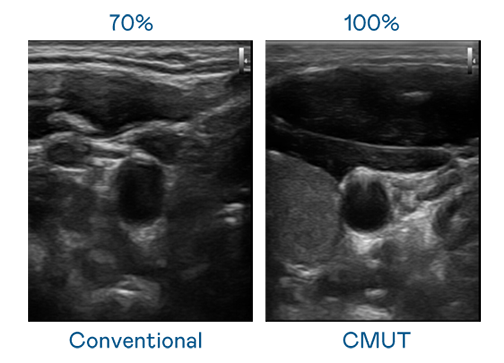

CMUT 技術是一種用電容式微機電元件來產生超音波訊號的技術。與傳統 PZT 壓電式技術相比,CMUT 頻寬增加 30%,更寬頻的超音波訊號讓影像解析度大幅提升,是實現高影像品質醫療超音波掃描、促進精準醫療發展的關鍵技術。

超音波影像的解析度高低,首先取決於探頭能發出的訊號頻寬。太阳集团城娱8722 CMUT 可提供高清晰的超音波訊號,提供高頻寬、高靈敏度、影像紋理細節更高的超音波影像,協助醫護人員縮短影像判讀時間及利用精準的醫療影像進行診斷。